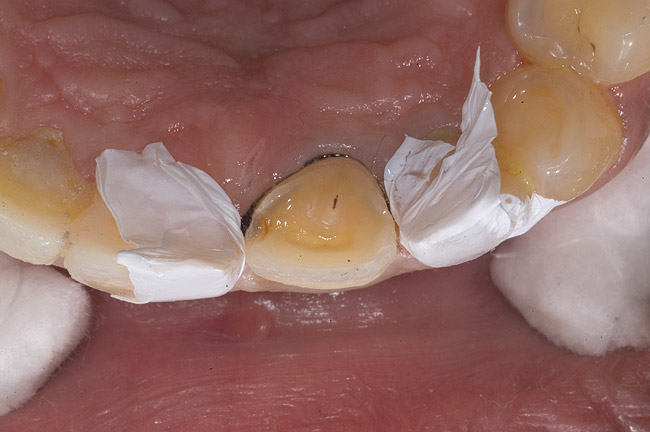

Figure 6  1:1 view demonstrating severe loss of tooth structure due to palatal erosion.

Figure 6

Figure 7  Palatal surface showing loss of form due to enamel dissolution.

Figure 7